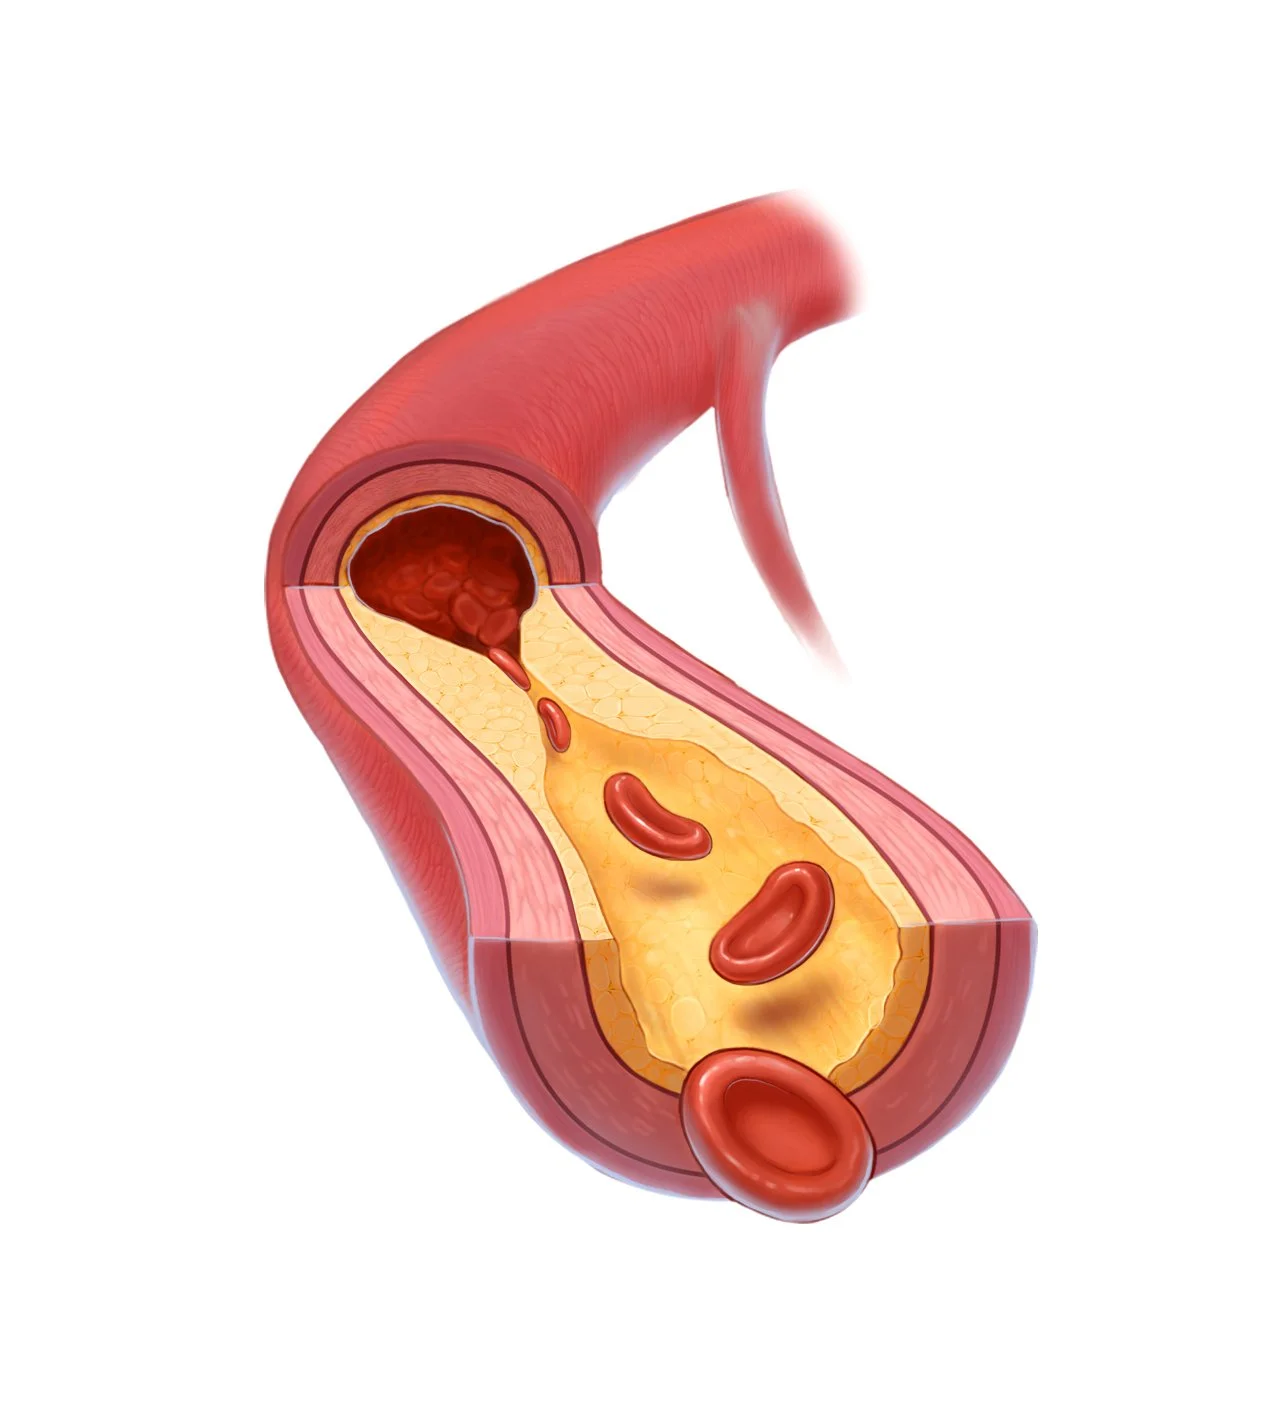

We are no strangers to the life sciences. Our medical animations animations can show how molecules interact in the body, how surgical procedures are performed, or how a new drug works at the cellular level. These visual aids help healthcare professionals, researchers, and patients understand complex medical concepts and procedures more easily.

We specialize in a wide variety of medical visual communications. Take a closer look:

Medical Illustration